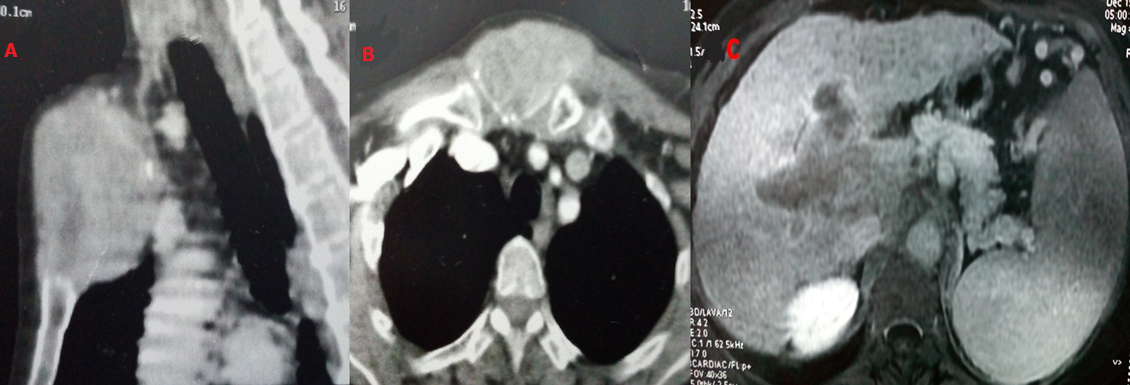

Nous rapportons le cas d'une femme âgée de 64 ans suivie pour hépatite virale C au stade de cirrhose ayant échoué au traitement antiviral. Lors de sa dernière consultation, la patiente a signalé l'apparition d'une voussure douloureuse thoracique antérieure. L'examen physique a révélé une masse dure et immobile en regard de l'articulation manubrio-sternale. Une tomodensitométrie (TDM) sterno-claviculaire a été réalisée, objectivant une lésion expansive ostéolytique centrée au niveau sur le manubrium sternal envahissant les parties molles (A, B) et dont la biopsie a révélé une tumeur maligne d'allure épithéliale d'architecture papillaire exprimant la pancytokératine et la CK7. Ce profil était évocateur d'une métastase d'un cholangiocarcinome ou d'un cancer ostéophile. Un examen gynécologique spécialisé avec une mammographie et une échographie mammaire ont éliminé une origine gynécologique. Une échographie cervicale a écarté une tumeur thyroïdienne. La TDM thoracique a révélé de multiples nodules pulmonaires d'allure secondaire. Un angioscanner abdominal a montré la présence d'une masse tissulaire hépatique de 6 cm envahissant la bifurcation portale avec thrombose porte évocatrice d'un carcinome hépatocellulaire (CHC) (C). Devant la contradiction discordance entre les données anatomopathologiques et morphologiques, une étude immunohistochimique par l'anti-Hep-Par-1 a été réalisée montrant une expression de cet anticorps par les cellules tumorales. Le diagnostic de métastase manubriosternale d'un carcinome hépatocellulaire peu différencié a été retenu. La patiente a été proposée pour chimiothérapie. Les métastases osseuses révélant un CHC sont exceptionnelles. Toutefois, il faut les évoquer devant toute lésion osseuse lytique, surtout chez les patients atteints d'hépatopathie chronique. Vu leur pronostic sombre, leur traitement est palliatif, visant essentiellement à améliorer la qualité de vie des patients.